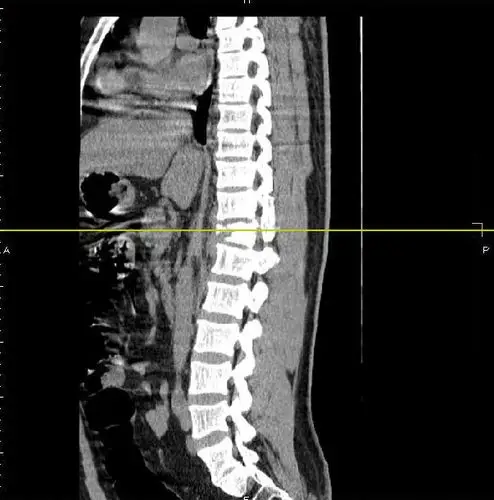

胸12椎体爆散骨折,胸髓损伤,双下肢不全瘫,胸腹联合切口 - 好大夫在线